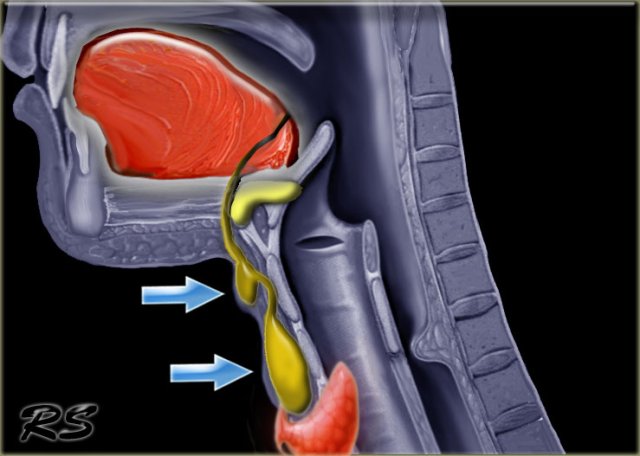

Multinodular goiter

Step 1: Which space

On the left a patient with a swelling on the left side of the neck, which has existed for years.

The swelling is adjacent to the left lamina of the thyroid cartilage.

The strap musculature seems to be draped over the lesion (blue arrow).

Therefore this lesion lies within the visceral space.

Step 3: Pattern recognition and clinical information

On the chest film we notice a displacement of the trachea to the right by an upper mediastinal mass.

So the mass is located within the visceral space and extends into the anterior mediastinum, since the trachea is located within the anterior mediastinum.

It is well-defined towards the surrounding fat and there are a few scattered coarse calcifications.

When we combine these findings, we recognize the radiological pattern of a benign multinodular goiter.

This diagnosis is compatible with the clinical information that the swelling in the neck has been present for years.